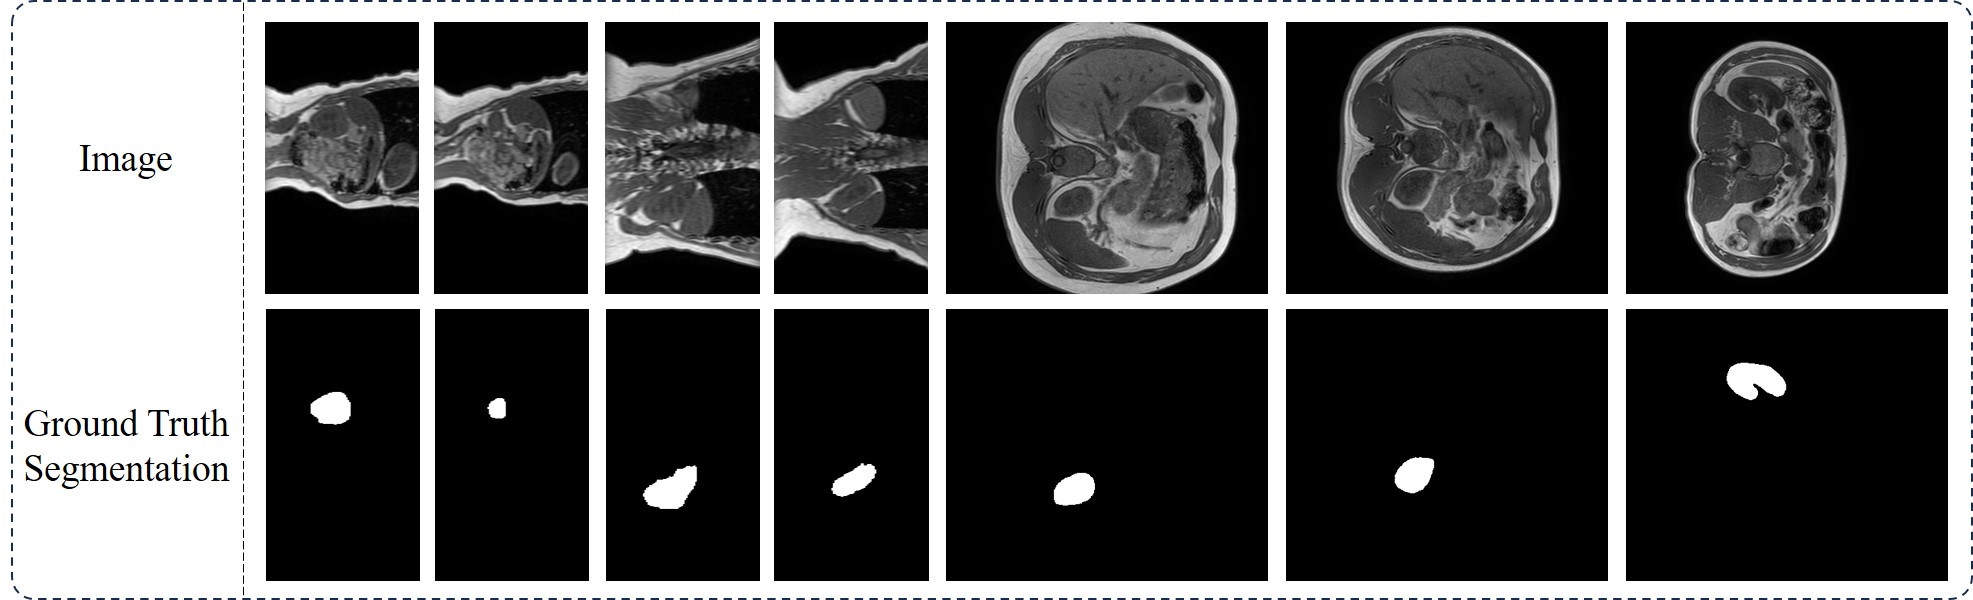

Refer to caption

Figure 3: Samples from the MRI-Kidney100 dataset

The 1st in-house dataset, named MRI-Kidney100, contains MRI scans from 100 individuals, designed for kidney segmentation. This dataset includes 100 3D MRI scans, from which 2D slices along the x-y plane were extracted for model testing. Similarly, the 2nd in-house dataset, named CT-BCT100, comprises CT scans from the same 100 individuals, focused on brachiocephalic trunk (BCT) segmentation. This collection includes 100 3D CT scans, with 2D slices from the x-y plane used for model testing. The 3rd in-house dataset, named Endo-Polyp1000, is a colonoscopy polyp detection dataset consisting of 1000 images, each paired with an expert-annotated mask. This dataset features a diverse range of polyp images. The 4th in-house dataset, named Path-Neuro1406, is a pancreatic neuroendocrine-related segmentation dataset with 1,406 images. In this dataset, we cropped the regions of interest from the large pathological sections stained with hematoxylin and eosin (H&E) according to doctor-annotated masks. The regions of interest vary significantly in shape and size, making segmentation particularly challenging. Image samples of these four in-house datasets can be found in Figures 345 and 6.